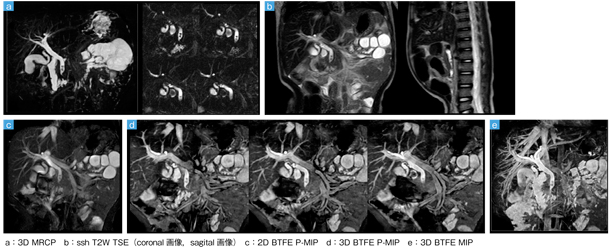

■症例4:総胆管結石(3歳,男児)のMRCP

■症例5:心筋症(1歳,男児)のシネMRI